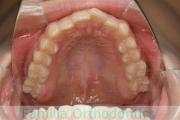

No.22V-759

- 主な症状:

- 叢生

- その他の症状:

- 上顎前突

- 年齢:

- 32歳

- 性別:

- 女性

- 抜歯部位

- 上:

- non

- 下:

- 主な使用装置:

- Invisalign

- 治療にかかった費用:

- 95万円

上の前歯の並びが気になるのできれいにしたい、ということで来院されました。マウスピース型矯正装置のひとつ、インビザライン/InvisalignR(薬機法および医薬品副作用被害救済制度の対象外)を用いて治療しました。

非抜歯で2年弱、20回程度の通院で治療が完了しました。

マウスピース矯正は、患者さんの協力に治療結果が左右されるところはリスクと言えるかもしれません。

- ≫治療前

-

上顎

下顎